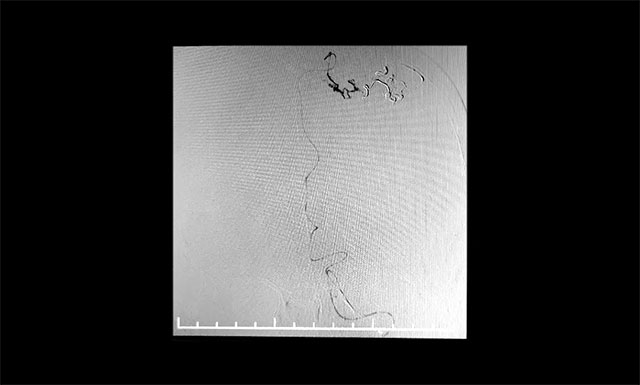

▲ 微导管造影确认后,注入 Onyx 18胶

张琪博士团队制定了严密的手术计划,预料各种术中、术后可能出现的意外及并发症。7月12日行动静脉畸形介入栓塞术,术中导管在动静脉畸形部位缓慢推注Onyx18生物胶,DSA透视下显示胶在畸形中弥散良好,无明显反流,顺利栓塞。